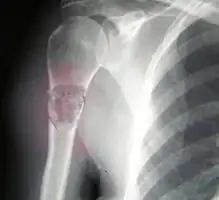

Osteosarcoma of the distal femur -

Telangiectactic osteosarcoma of the humerus